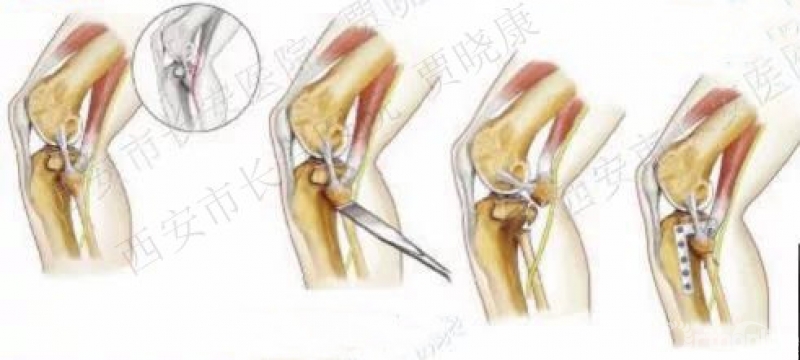

(二)截骨入路

1. 腓骨头截骨

2010年

2008年禹宝庆

适用于41B2.1x或u并t,41B3.1x或u并t。

这种方法单独或结合后内侧入路治疗胫骨平台骨折8例。

2. 腓骨颈截骨入路1

2012年庄岩

原文:17例胫骨平台后外侧骨折患者。膝关节外侧经腓骨头的纵形切口,近端起自腓骨头上方10cm,向远端垂直延伸10-15cm。